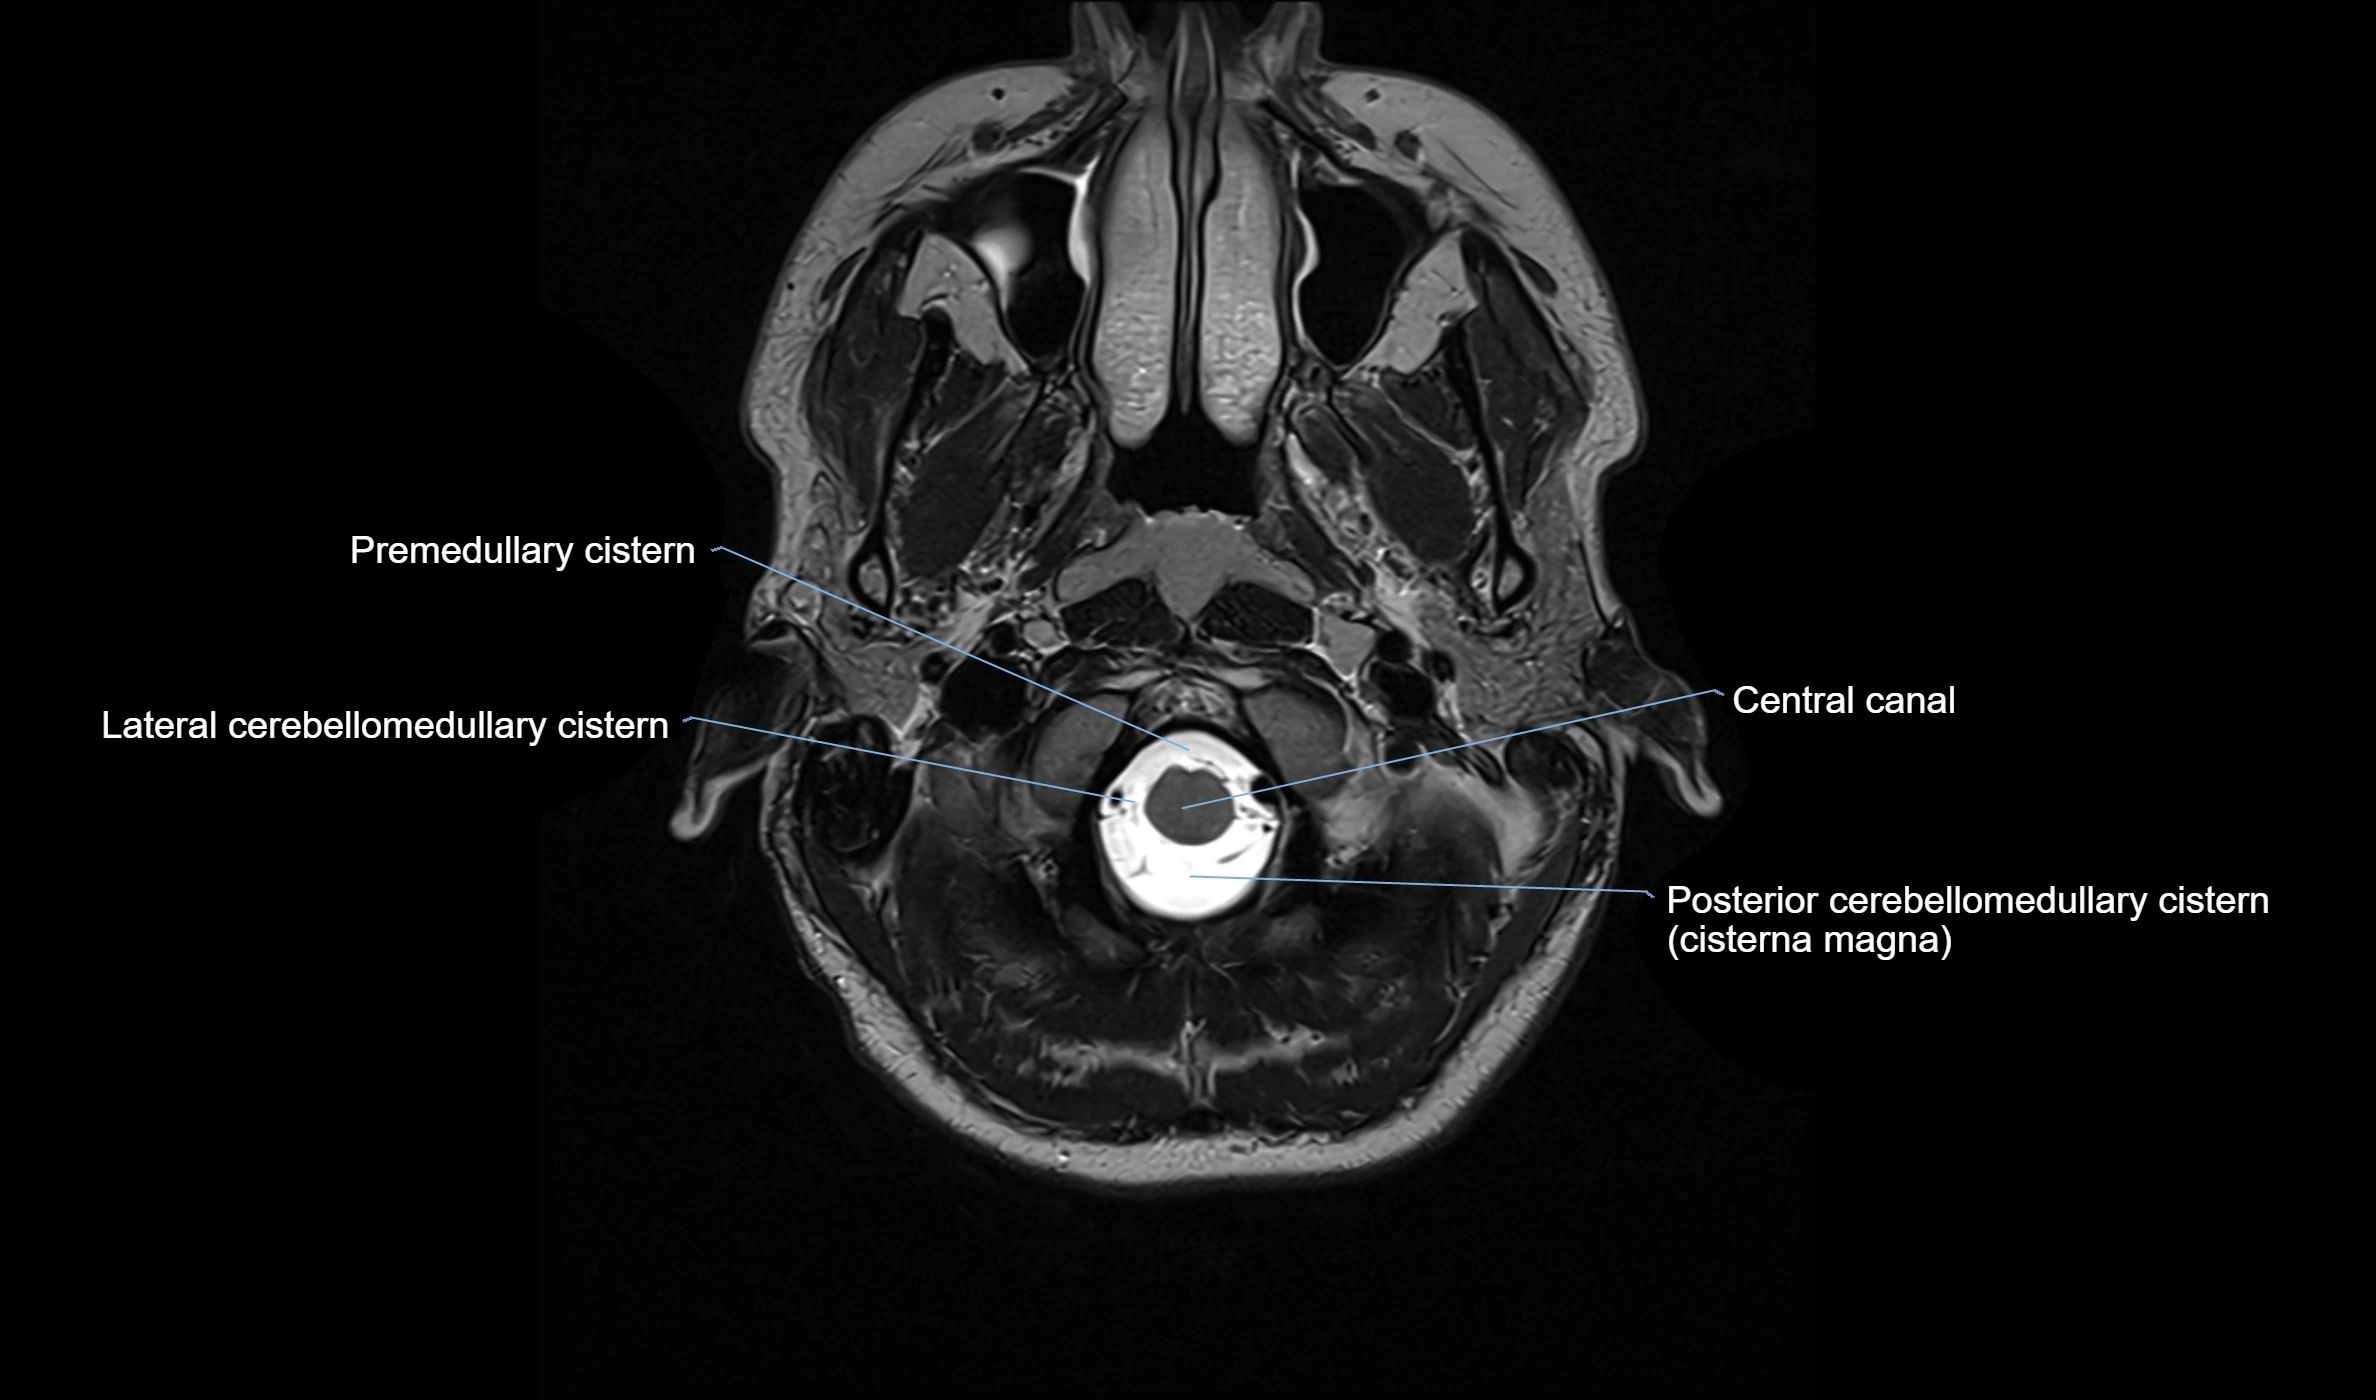

MRI images

image